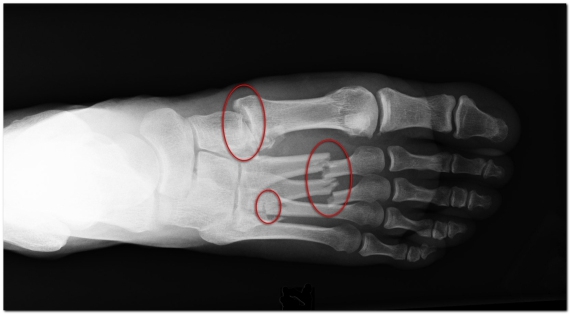

Диагностика

При диагностике перелома плюсневых костей учитываются анамнез (наличие травмы), жалобы пациента, результаты объективного осмотра стопы и данные рентгенологического исследования.

Рентгенологическое обследование. При наличии подозрений на перелом пятой плюсневой кости выполняется рентгенография стопы в трех проекциях: переднезадней, боковой и косой.